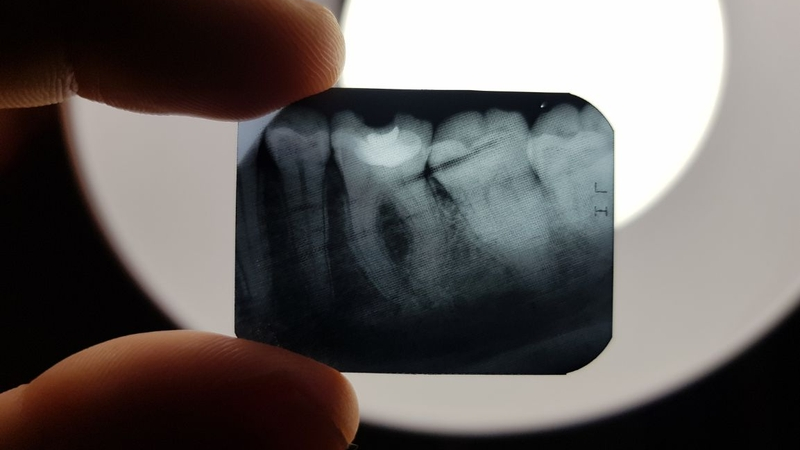

Máy scan răng cận chóp (X-quang răng cận chóp) là phương tiện chẩn đoán hình ảnh giúp bác sĩ “nhìn xuyên” được toàn bộ thân răng, chân răng và phần xương quanh chóp răng trên một vùng rất nhỏ, thường chỉ 1–3 răng. Khác với phim toàn cảnh, phim cận chóp tập trung vào chi tiết, cho hình ảnh rõ nét từng chân răng, vùng chóp và cấu trúc xương xung quanh, từ đó phát hiện chính xác những tổn thương mà mắt thường không thể nhìn thấy

Nhờ độ chi tiết này, bác sĩ có thể đánh giá đúng tình trạng viêm, sâu, tổn thương xương hay các bất thường quanh chóp răng, tránh tình trạng “điều trị mò”, giúp phác đồ điều trị tại Zensmile luôn rõ ràng, minh bạch và an toàn cho khách hàng.

Trong điều trị nội nha (chữa tủy), phim răng cận chóp gần như là “bắt buộc”. Bác sĩ dựa vào phim để đánh giá chiều dài chân răng, hình dạng ống tủy, tình trạng xương quanh chóp, sau đó mới quyết định cách xử lý. Nếu không có phim, việc điều trị sẽ thiếu chính xác, có nguy cơ sót tủy, đau kéo dài hoặc phải điều trị lại.

Trước khi nhổ răng khôn, nhổ răng sâu hoặc răng gãy sát lợi, phim cận chóp giúp bác sĩ xác định hình dạng chân răng, mức độ cong, vị trí so với các cấu trúc xung quanh. Nhờ đó, quá trình tiểu phẫu được lên kế hoạch kỹ càng hơn, thao tác “êm” hơn, giảm sang chấn không cần thiết.

Trong cấy ghép Implant hoặc phục hình răng sứ trên vùng ít răng, phim cận chóp cho phép xem mật độ và chiều cao xương quanh vùng cần điều trị, kiểm tra tình trạng các răng bên cạnh, từ đó đưa ra phương án an toàn và tối ưu lâu dài. Thậm chí, ở những khách có bệnh lý nha chu (tiêu xương, tụt lợi), phim cận chóp cũng giúp bác sĩ đánh giá mức độ tiêu xương quanh răng để tư vấn giữ hay nhổ răng một cách rõ ràng, có căn cứ.